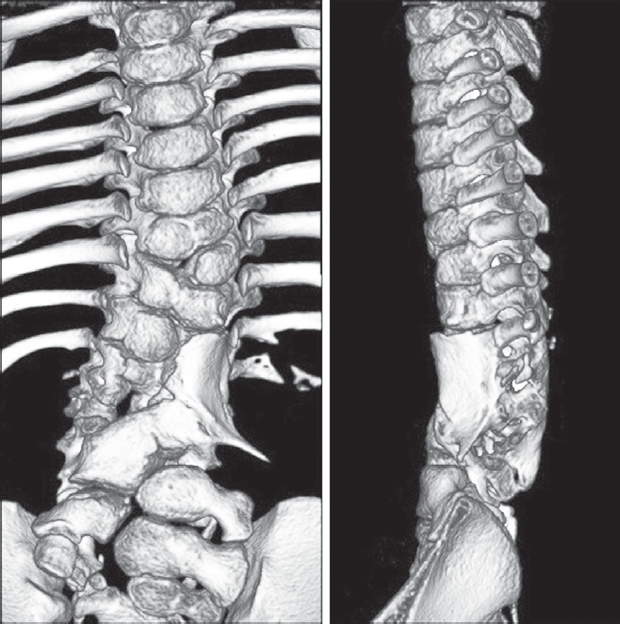

При контрольной компьютерной томографии через 18 месяцев выявлено приживление трансплантата и формирование сплошного костного блока в зоне вмешательства, обеспечивающее стабильность поясничного отдела позвоночника и низкий потенциал прогрессии кифоза (рис. 3). С точки зрения неврологического дефицита отмечено некоторое улучшение с сохранением нижнего парапареза (больше справа; Frankel D). По данным магнитно-резонансной томографии через 25 месяцев после операции признаков компрессии невральных структур не получено. Оперативное лечение, в том числе декомпрессия и/или мобилизация спинного мозга, в настоящее время не показано. Вместе с тем, учитывая возраст ребенка (5 лет) и потенциал роста, необходимы медицинское сопровождение и регулярные контрольные неврологические и лучевые обследования до окончания костного роста.

Рис. 3. Компьютерная томография через 18 месяцев после операции. Сформирован костный блок в зоне оперативного вмешательства: a — вид спереди; b — вид слева